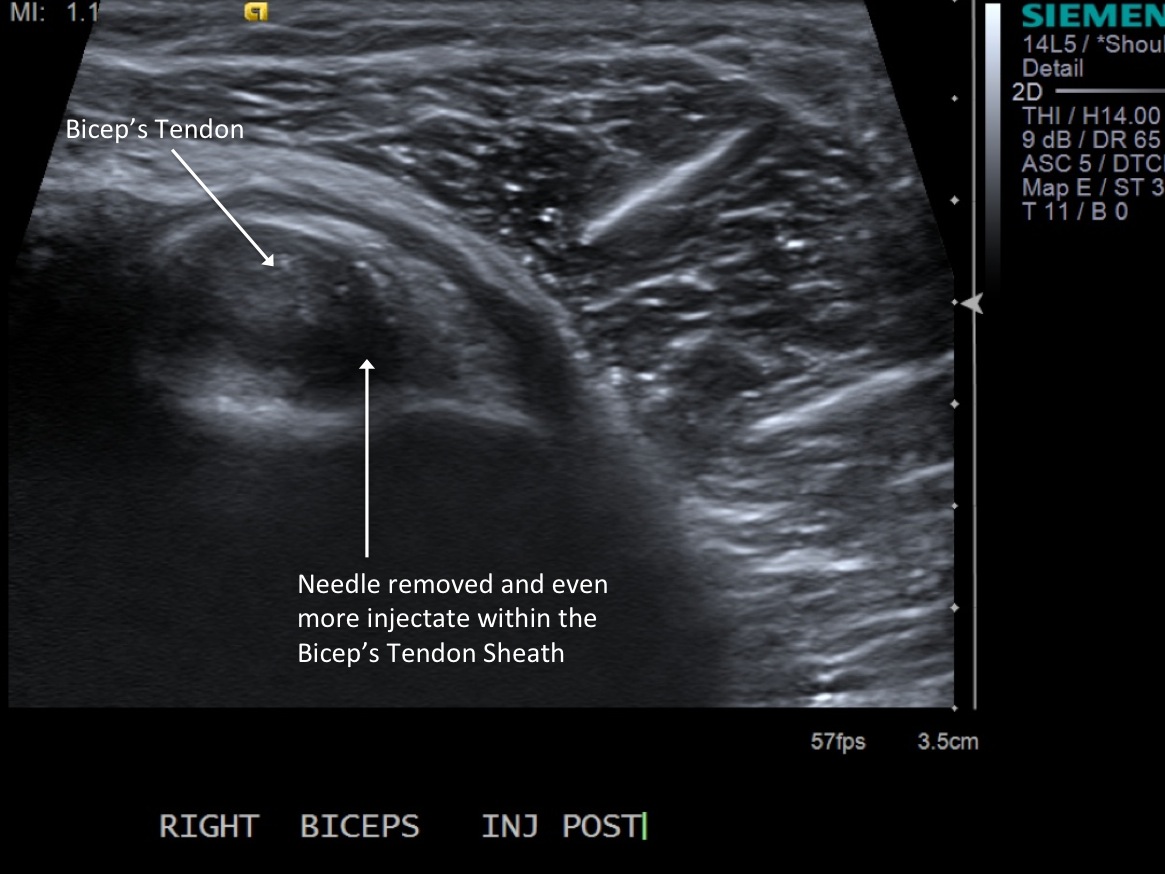

12. Scan sheath to demonstrate distention.

• descriptiondescription